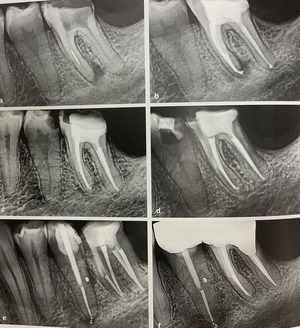

難しい根管治療の歯

左の根っこに器具が折れてますね。

真っ白に見えるのです。

それを取って、根管充填して

すぐにコア、頭部分を補強して、レジンで詰めて

紹介元の先生へ戻って頂きます。

4年後に根管治療の確認にいらしたのが、真ん中の左?

被せてない?

で、11年後、

隣の小臼歯が痛くなって来られたのが、右。